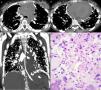

Imágenes de la tomografía axial computarizada a nivel de la bifurcación bronquial (A) y los lóbulos inferiores (B), e imagen coronal reformateada (C) que muestran varios nódulos calcificados en las regiones subpleurales y a lo largo de las fisuras. También se observan calcificaciones en los ganglios linfáticos mediastínicos y derrame pericárdico. D) Sección histológica que muestra la proliferación de células neoplásicas con formación de tejido óseo. También se observan atipias nucleares (hipercromasia y cariomegalia); (tinción de hematoxilina y eosina, ×400).

Una niña de 14 años de edad fue hospitalizada por presentar inflamación dolorosa de la rodilla izquierda de 30 días de evolución, que no había mejorado con analgésicos y antiinflamatorios no esteroideos. La radiología mostró una lesión osteolítica agresiva en el fémur distal izquierdo. El examen de la biopsia abierta reveló una proliferación de osteoblastos neoplásicos con una abundante matriz irregular. El diagnóstico fue de osteosarcoma. La paciente inició quimioterapia, pero no mostró buena respuesta al tratamiento y la enfermedad permaneció estable. Cinco meses después del diagnóstico, la paciente presentó dolor torácico y distrés respiratorio. La tomografía computarizada torácica reveló varios nódulos calcificados irregulares y placas en las regiones subpleurales de los pulmones, y un derrame pericárdico (fig. 1). La toracoscopia mostró numerosos nódulos subpleurales. El diagnóstico histopatológico fue de osteosarcoma metastásico. Pocos días después la paciente presentó disnea intensa y empeoramiento de su estado general y falleció. La necropsia confirmó la diseminación linfática de células tumorales.

Las metástasis pulmonares por diseminación hematógena del osteosarcoma son frecuentes, pero la carcinomatosis linfangítica de este tipo tumor es muy infrecuente. La invasión y desarrollo retrógrado del tumor en el intersticio linfático y perilinfático produce la diseminación del tumor a lo largo del septo interlobular, las fisuras y las superficies pleurales de los pulmones y sin metástasis nodulares, como observamos en nuestra paciente. También puede observarse la afectación de ganglios linfáticos, con metástasis calcificadas1,2.